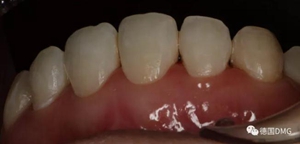

術(shù)后顯示,滲透樹(shù)脂恢復(fù)了天然牙釉質(zhì)的折光率(天然通透牙釉質(zhì)折光率1.62滲透樹(shù)脂折光率是1.52)顯的很自然,很有光澤。完全是天然牙質(zhì)的顏色。

(下圖是拋光完成)

治療前和治療后的對(duì)比,患者很高興很滿(mǎn)意。